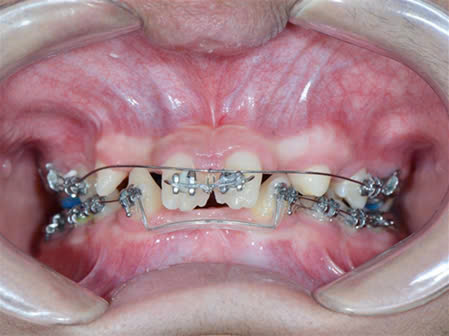

Kết hợp giữa chỉnh nha và phục hình implant: để sắp đều răng và phục hình các răng thiếu trên cung hàm.

Ở nha khoa Như Ngọc, chúng tôi đang phối hợp điều trị và theo dõi cho bệnh nhân nhân loạn sản ngoại bì.

Đối với điều trị răng cho các bé từ giai đoạn ban đầu hàm giả tháo lắp giúp phục hồi chức năng ăn nhai cũng như phát âm, giao tiếp cho trẻ 1 cách tốt nhất.

Làm hàm giả tháo lắp cho trẻ.

Nhờ hàm giả mới này, khuôn mặt của trẻ thay đổi về ăn nhai cũng như mặt thẫm mỹ.